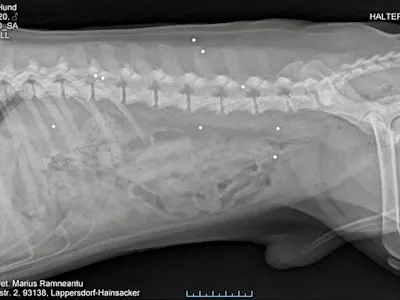

Unser süßer Lorenzo hat 2022 in Bayern sein endgültiges Zuhause gefunden. Es geht ihm sehr gut, die Leishmaniose-Therapie mit Allopurinol und Letifend war ein voller Erfolg. Er lebt in einem Haushalt mit 5 weiteren Hunden und ist bestens integriert. Er liebt seine Gassigänge und er liebt das Meer - wenn es denn nicht zu aufgewühlt ist. Bei einem Tierarztbesuch wurde eher zufällig entdeckt, dass Lorenzo eine ganze Ladung Schrotkugeln im Körper hat - man mag sich nicht vorstellen, was der kleine Kerl schon alles durchgemacht hat.

Die unter Narkose angefertigten Röntgenbilder brachten es dann ans Licht....eine deutliche HD macht ihm das Leben schwer. Da Lorenzo für eine Femurkopfresektion noch zu jung und die HD auch noch nicht extrem weit fortgeschritten ist versuchen wir nun, ihm mit einer PRP (plättchenreiches Plasma) Erleichterung zu verschaffen. Sollten die dafür notwendigen 3 Behandlungen nicht anschlagen, steht als Alternative eine Hyaluron Injektion ins Gelenk auf dem Plan. Als wäre der arme Tropf mit seiner Leishmaniose noch nicht genug geplagt – auch hier steht im April noch erneut die Kontrolle der aussagekräftigen Blutwerte auf dem Plan.